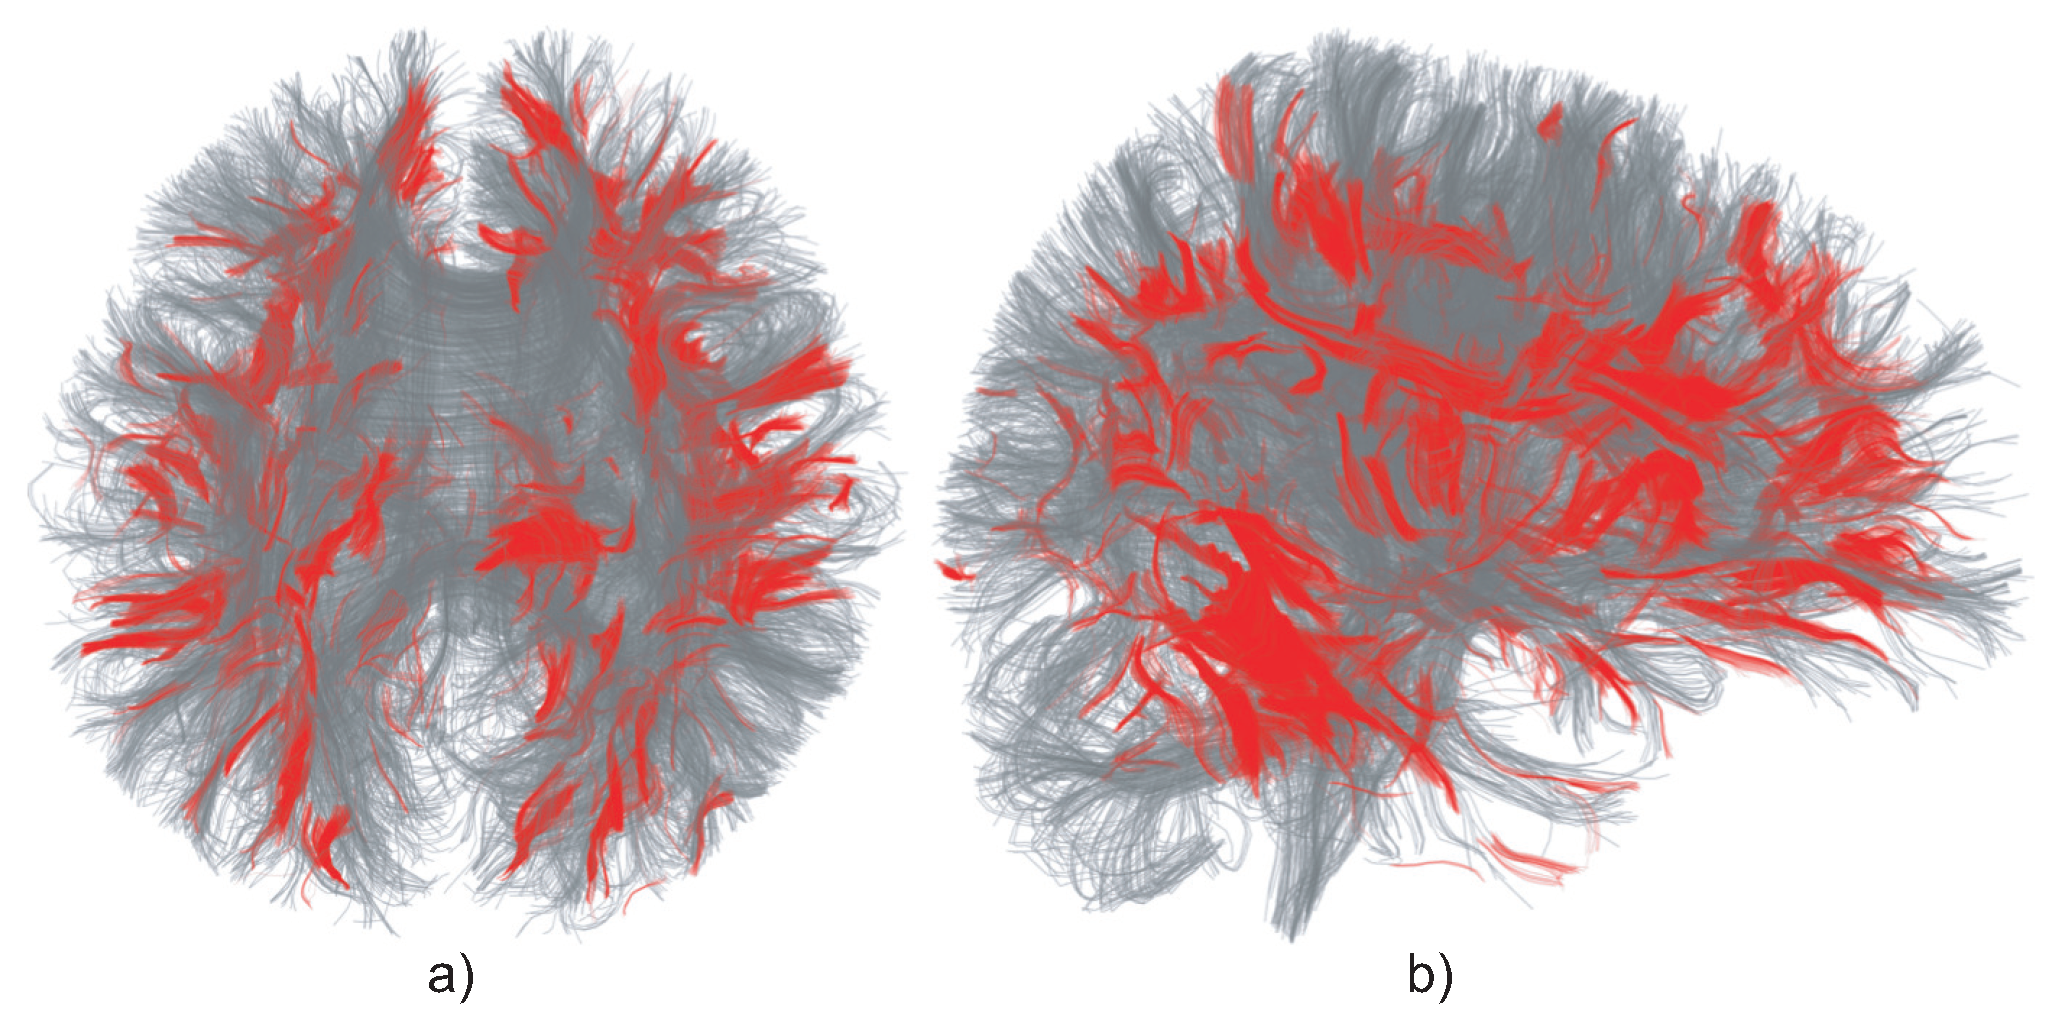

Similar to Vilanova et al. [20], we use the constraints c p 0.25 and c l 0.2 to find the seeding region, and trace fibers, randomly seeded at voxels in these regions, until they exit them, i.e., not meet the above-mentioned constraints. Fiber tracking is done using Euler integration along the major eigenvector of the DTI tensor, and trilinear interpolation. Figure 6 shows the effect of reseeding of a relatively small 15 K trail set. Reseeding adds a total of 65 K trails (marked in red) to the original 15 K ones (marked in gray).